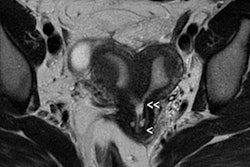

They found BLADE significantly (p < 0.0001) reduced motion and ghosting artifacts and showed improved conspicuity, but overall image quality did not differ significantly in the 47 patients who underwent sagittal BLADE and conventional TSE at 1.5-tesla after glucagon administration. In the majority of cases (53.2% versus 59.6%), radiologists preferred conventional TSE due to better image contrast and visibility of free pelvic fluid. Signal-to-noise ratio (SNR) and contrast-to-noise ratio (CNR) were significantly higher on conventional TSE.

"In our comparative study, the overall image contrast was reduced when using BLADE. This might be explained with the nonuniform T2-weighting along the width of the blade, i.e., the phase-encoding direction with contrast predominantly determined by low-frequency data as described by Pandit et al," Froehlich and colleagues wrote. "The reduced SNR and CNR in BLADE images occurred despite more frequent sampling of the k-space center. This was likely because the bandwidth in BLADE was twice as large as in conventional TSE (260 Hz per pixel in BLADE compared with 130 Hz per pixel in conventional TSE)."

"Indeed, conventional T2-weighted TSE provided a significantly better visibility of free pelvic fluid or cystic structures (i.e., a relatively higher effective T2 weighting) in numerous cases," the researchers noted.

BLADE improves anatomic depiction and image quality thanks to less movement artifact, but at the expense of CNR of cystic structures or visibility of free pelvic fluid.